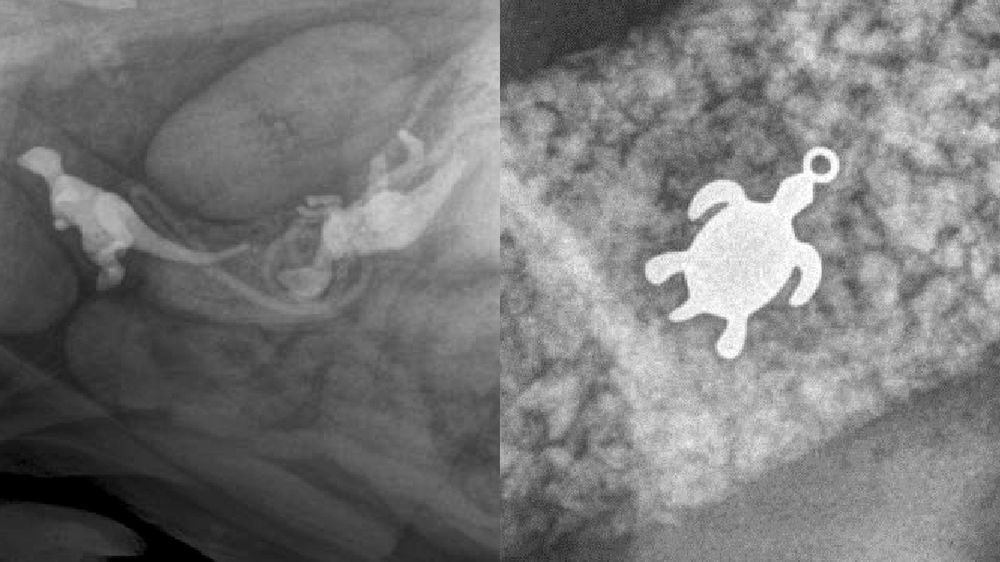

/ 11Żółwik

Obraz

© Veterinary Practice News / Don Harris, DVM, of Avian & Exotic AMC in Miami

Drugie miejsce należy do Loli, 7-kilogramowej żółwicy. Z przedłużającym się brakiem apetytu trafiła do weterynarza, a ten na zdjęciu rentgenowskim odkrył źródło problemu - połknięty wisiorek z... żółwiem wielkości 15 mm. Po operacji Lola wróciła w pełni do zdrowia.